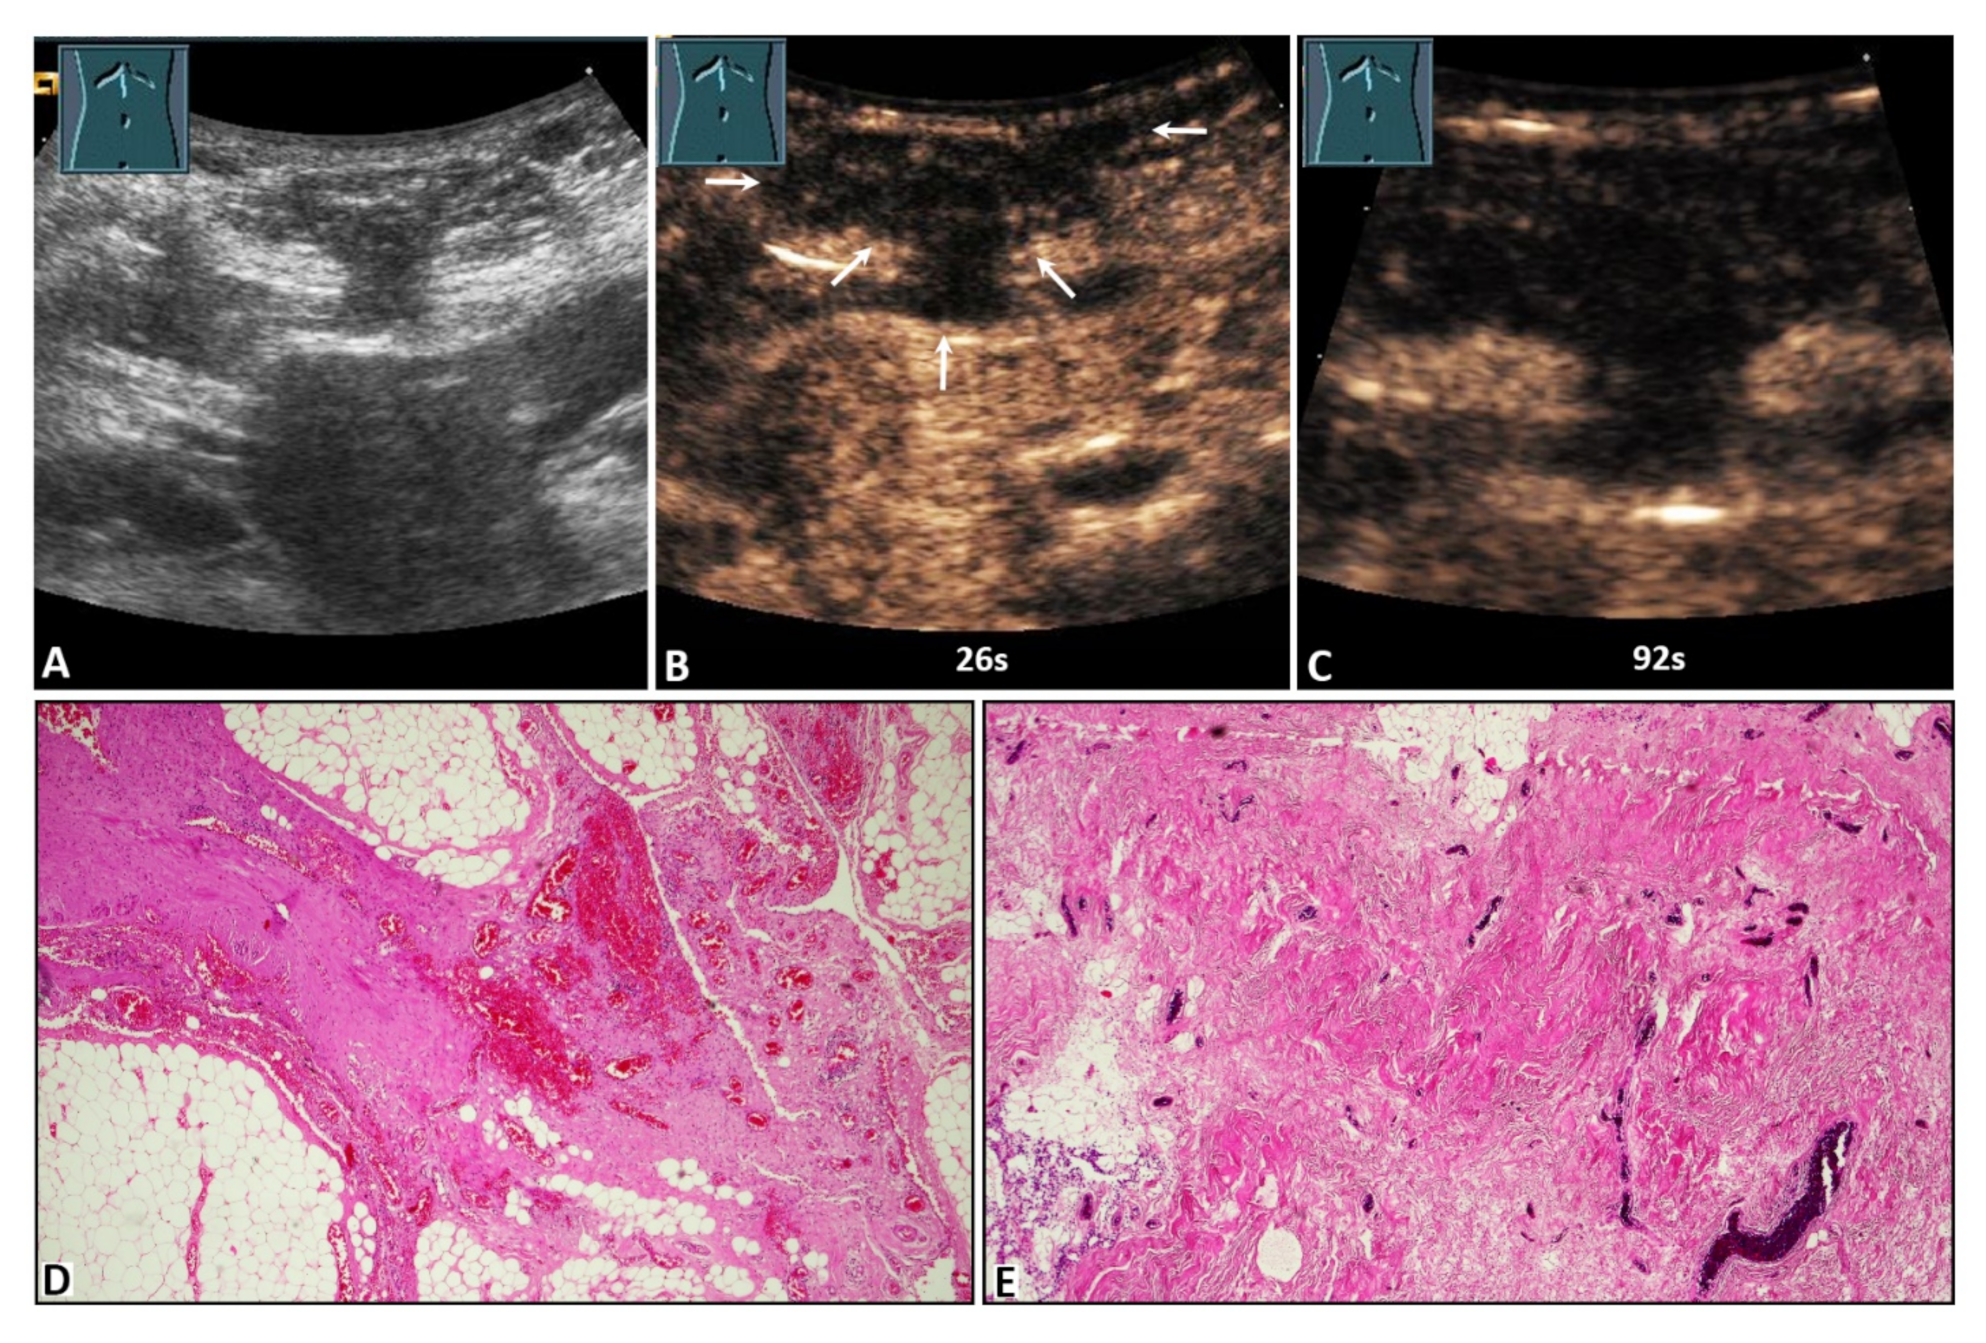

Figure 4.

A 59-year-old male patient with acute peritoneal pain in the umbilical region and a palpable tumor. (A) B-mode ultrasound shows a complex lesion located in the abdominal wall, with visualization of omental hernia content. (B,C) On contrast-enhanced ultrasound, the lesion shows absent enhancement after 26 s (arrows) and 92 s. (D) Omentum with fibrotic strands, including dilated hyperemic capillaries (4× magnification). (E) Fibrotic hernia sac with dilated hyperemic capillaries (10× magnification).